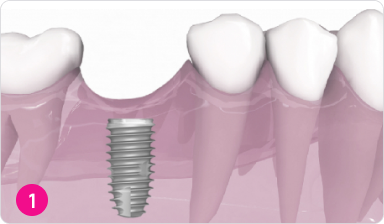

Установка зубного имплантата

(искусственного корня)

Во время первой процедуры имплантата устанавливается в наиболее подходящем положении